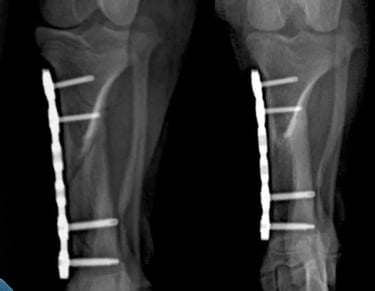

Un sistema de placa bloqueada es una técnica avanzada de fijación interna en la que los tornillos se bloquean directamente a la placa, formando una estructura rígida y estable.

A diferencia de las placas convencionales, este sistema no depende de la compresión contra el hueso, lo que permite:

Inserción de tornillos bloqueados

Los tornillos se introducen atravesando la placa y se enroscan en ella, quedando firmemente anclados tanto al hueso como a la placa.

Formación de un sistema rígido

Al bloquearse los tornillos con la placa, se crea una estructura estable tipo “armazón” que no depende de la presión sobre el hueso.